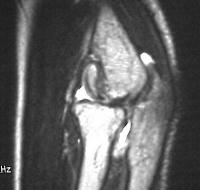

MRI shows an osteochondral sequestrum of the anterior capitellum: